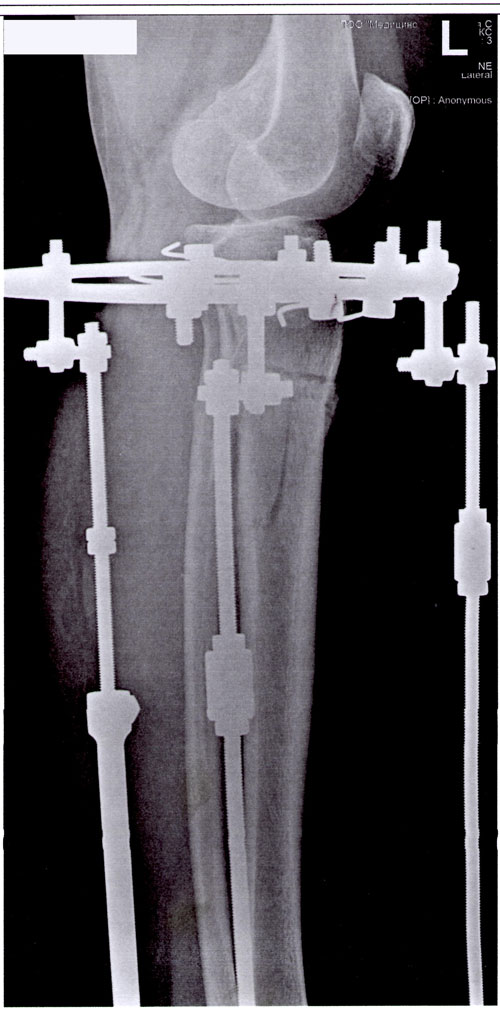

Отправляю вам контрольные рентген-снимки и фото ножек. Со дня снятия прошло 50 дней.

Здравствуйте, Наталья! По рентгену, всё отлично! разрешено всё без ограничений! Исключить: беременность в течении первых 6 месяцев.